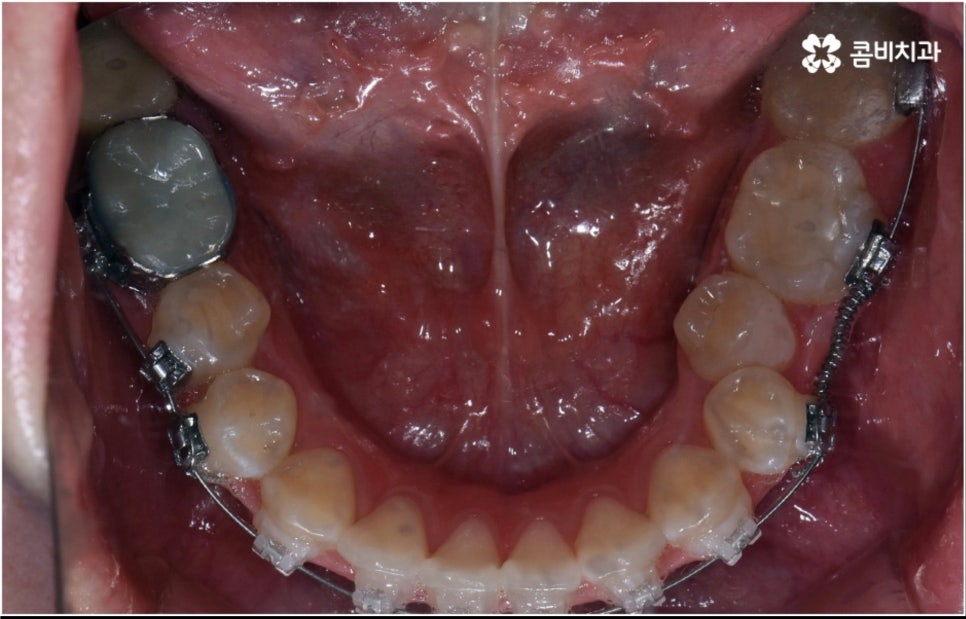

3D CT 등 정밀 검진 기계를 통해 꼼꼼하게 검진을 한 후 환자분들의 부정교합의 종류 및 정도 등에 따라 각자에게 맞는 교정 치료 계획을 수립하게 되는데, 내부 공간이 얼마나 있는지에 따라 발치가 필요한지 아닌지 여부도 달라지고 또 같은 부정교합이라고 해도 사람마다 잇몸 건강이나 치근 상태 등에 따라 잇몸뼈가 벌어지면서 치아가 이동하는 속도, 치아가 자리잡는 양상 등도 모두 달라지기 때문에 성인 치아교정 기간 총 소요 시간은 모두 달라질 수 밖에 없을 거예요.

하지만 부정교합의 정도가 심하거나 골격적 문제를 바로잡아 주어야 하는 경우는 전체 교정을 진행해야 하기 때문에 (환자분들마다 다르지만) 평균적으로 18~36개월 정도의 성인 치아교정 기간 이 소요되며, 중장년 성인분들 중에 잇몸 질환 등으로 구강 건강이 약해져 있는 분들의 경우에는 더욱 환자분들의 상황에 맞게 필요한 치료를 병행하면서 무리하지 않은 진행을 해야 하기 때문에 전체 기간이 좀 더 늘어날 수 있어요.

치아 색상의 세라믹 브라켓을 이용하는 장치들은 예전 메탈 장치 보다 심미성이 훨씬 보완되었으며, 치아 뒤쪽에 장치를 부착하여 아예 눈에 띄지 않는 설측교정장치나 언뜻 보면 티가 잘 나지 않는 얇고 투명한 특수 강화 플라스틱을 이용하는 투명교정장치를 이용하면 교정을 하고 있다고 본인이 말을 하지 않으면 잘 모를 정도로 심미성이 뛰어나기 때문에 각 장치들의 소재와 특성, 장단점에 대해서 잘 알아보고 신중한 선택을 하는 것이 중요하다고 할 수 있어요.